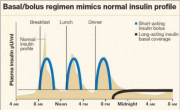

| 05:15, 14 באוגוסט 2023 | סוגי אינסולין1.png (קובץ) |  |

137 קילו־בייטים | Motyk | 1 | |